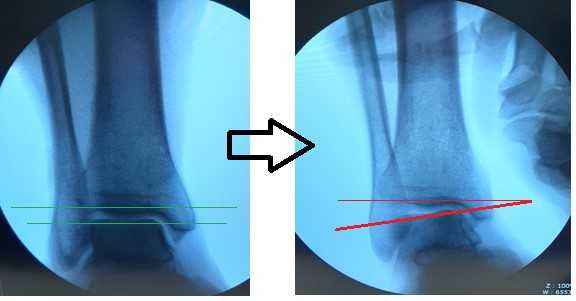

Для подтверждения механической нестабильности выполнены стресс-рентгенограммы голеностопного сустава с «варус-стресс тестом» и «тестом переднего выдвижного ящика». Критериями для постановки диагноза нестабильности является ангуляция таранной кости в коронарной плоскости более 4 градусов и смещение таранной кости кпереди в сагиттальной плоскости на 4 мм, или разница с контрлатеральной стороной в 2 градуса и 2 мм соответственно.

Если с варус-стресс тестом всё очень наглядно, оценивать передний выдвижной ящик рентгенологически чуть сложнее. Для этого можно либо обозначить центр купола таранной кости и встречной суставной поверхности большеберцовой кости точками и сравнивать расстояние между ними с или без нагрузки в задне-переднем направлении, либо использовать в качестве вспомогательного ориентира тень медиальной лодыжки и расстояние от неё до начала шейки таранной кости.